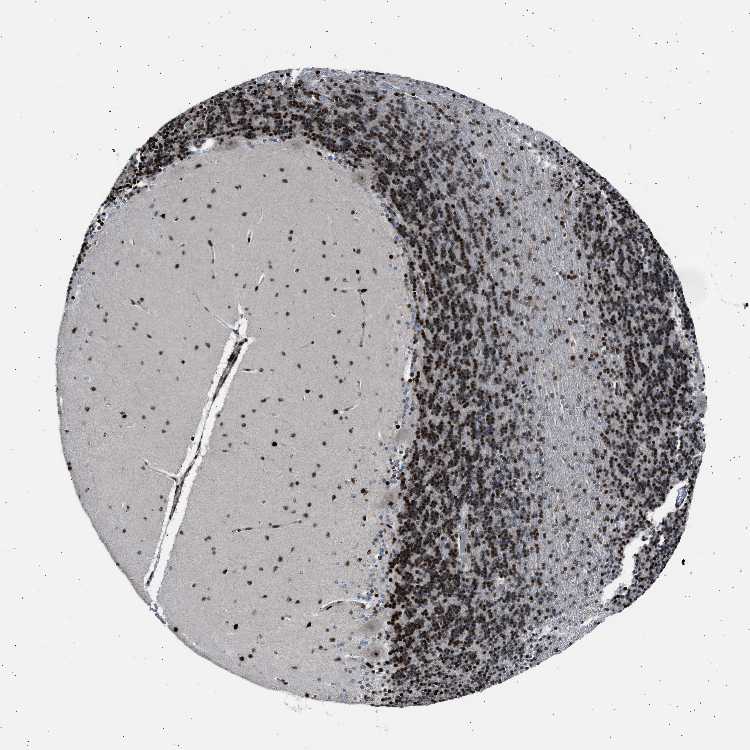

CEREBELLUM - Antibody stainingi

Antibody staining in the annotated cell types in the current human tissue is reported as not detected, low, medium, or high, based on conventional immunohistochemistry profiling in selected tissues. This score is based on the combination of the staining intensity and fraction of stained cells.

Each image is clickable and will lead to virtual microscopy that enables deeper exploration of all samples and also displays staining intensity scores, fraction scores and subcellular localization as well as patient and tissue information for each sample.

Antibody HPA015324

Purkinje cells High

Cells in granular layer High

Cells in molecular layer High